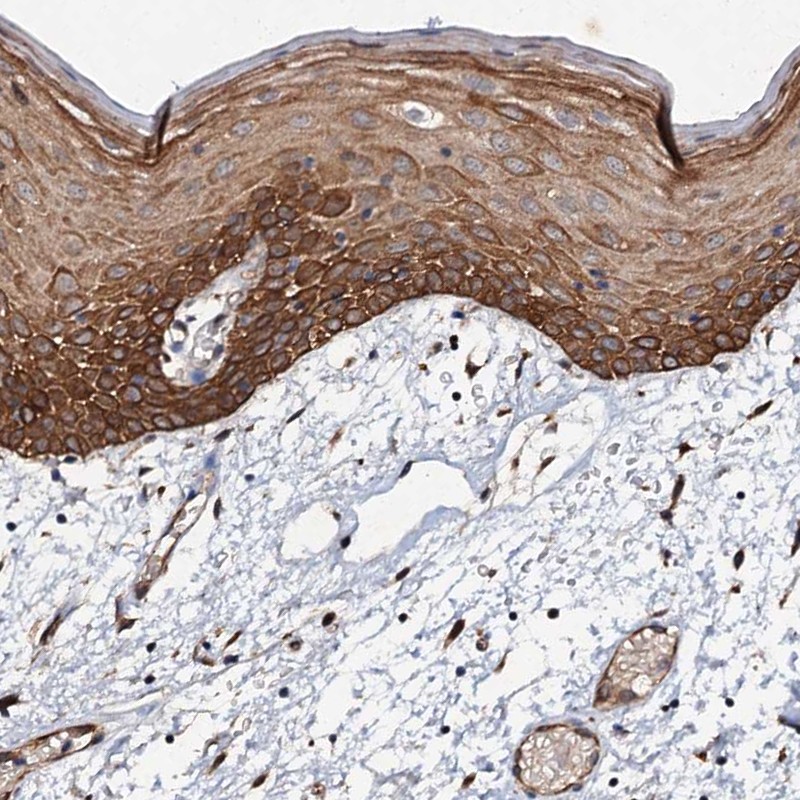

Immunohistochemical staining of human oral mucosa shows strong cytoplasmic positivity in squamous epithelial cells.